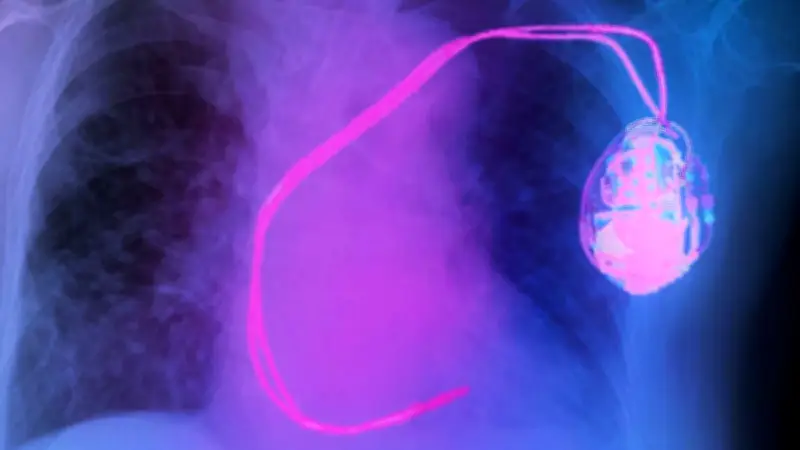

Der dreijährige Cameron aus Philadelphia benötigte dringend einen Herzschrittmacher, doch handelsübliche Modelle passten nicht zu seiner Körpergröße. Dr. Maully Shah vom Children's Hospital of Philadelphia erklärte das Dilemma: „Keines dieser Geräte ist für Kinder hergestellt oder für die Körpergröße von Kindern ausgelegt.“ Das medizinische Team entschied sich für eine spezielle Miniatur-Version, die etwa die Größe einer AAA-Batterie aufweist.

Dieser winzige Herzschrittmacher musste individuell für Cameron angepasst werden, da weltweit nur etwa zehn Kinder mit einem solchen Gerät versorgt wurden. Dr. Shah betonte die Einzigartigkeit der Situation: „Dies ist eine einzigartige Situation, da Cameron eines von weltweit nur zehn Kindern ist, die einen solchen Herzschrittmacher erhalten.“ Das implantierte Gerät sendet elektrische Impulse an das Herz und übernimmt so die Steuerung des Herzschlags.